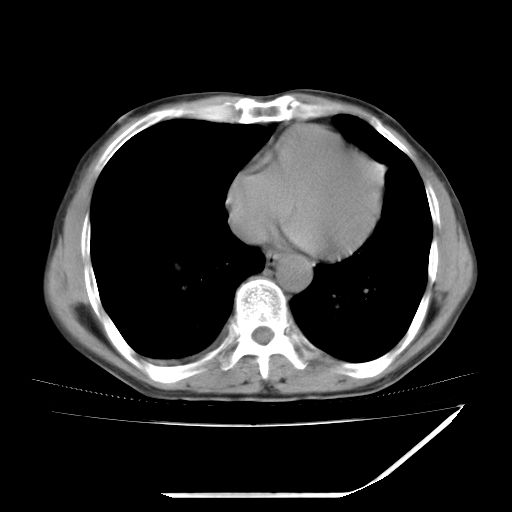

男,59岁,“结核性胸膜炎”30余年,胸部经常疼痛,多次x检查提示“肺部”炎症。腹部疼痛5日,b超提示:“肝内短管结石,余显示不清,建议进一步检查。”

两肺结核并右侧胸腔积液;脾脏、腹腔及腹膜后淋巴结结核[陈旧性];肝内胆管结石

胸部腹部都是结核(双肺。纵隔淋巴结,肝脏,脾脏,肠系膜)

两肺结核并右侧胸腔积液;脾脏、腹腔及腹膜后淋巴结结核[陈旧性];肝内胆管结石。直肠息肉?

均为结核所致,右侧少量胸腔积液